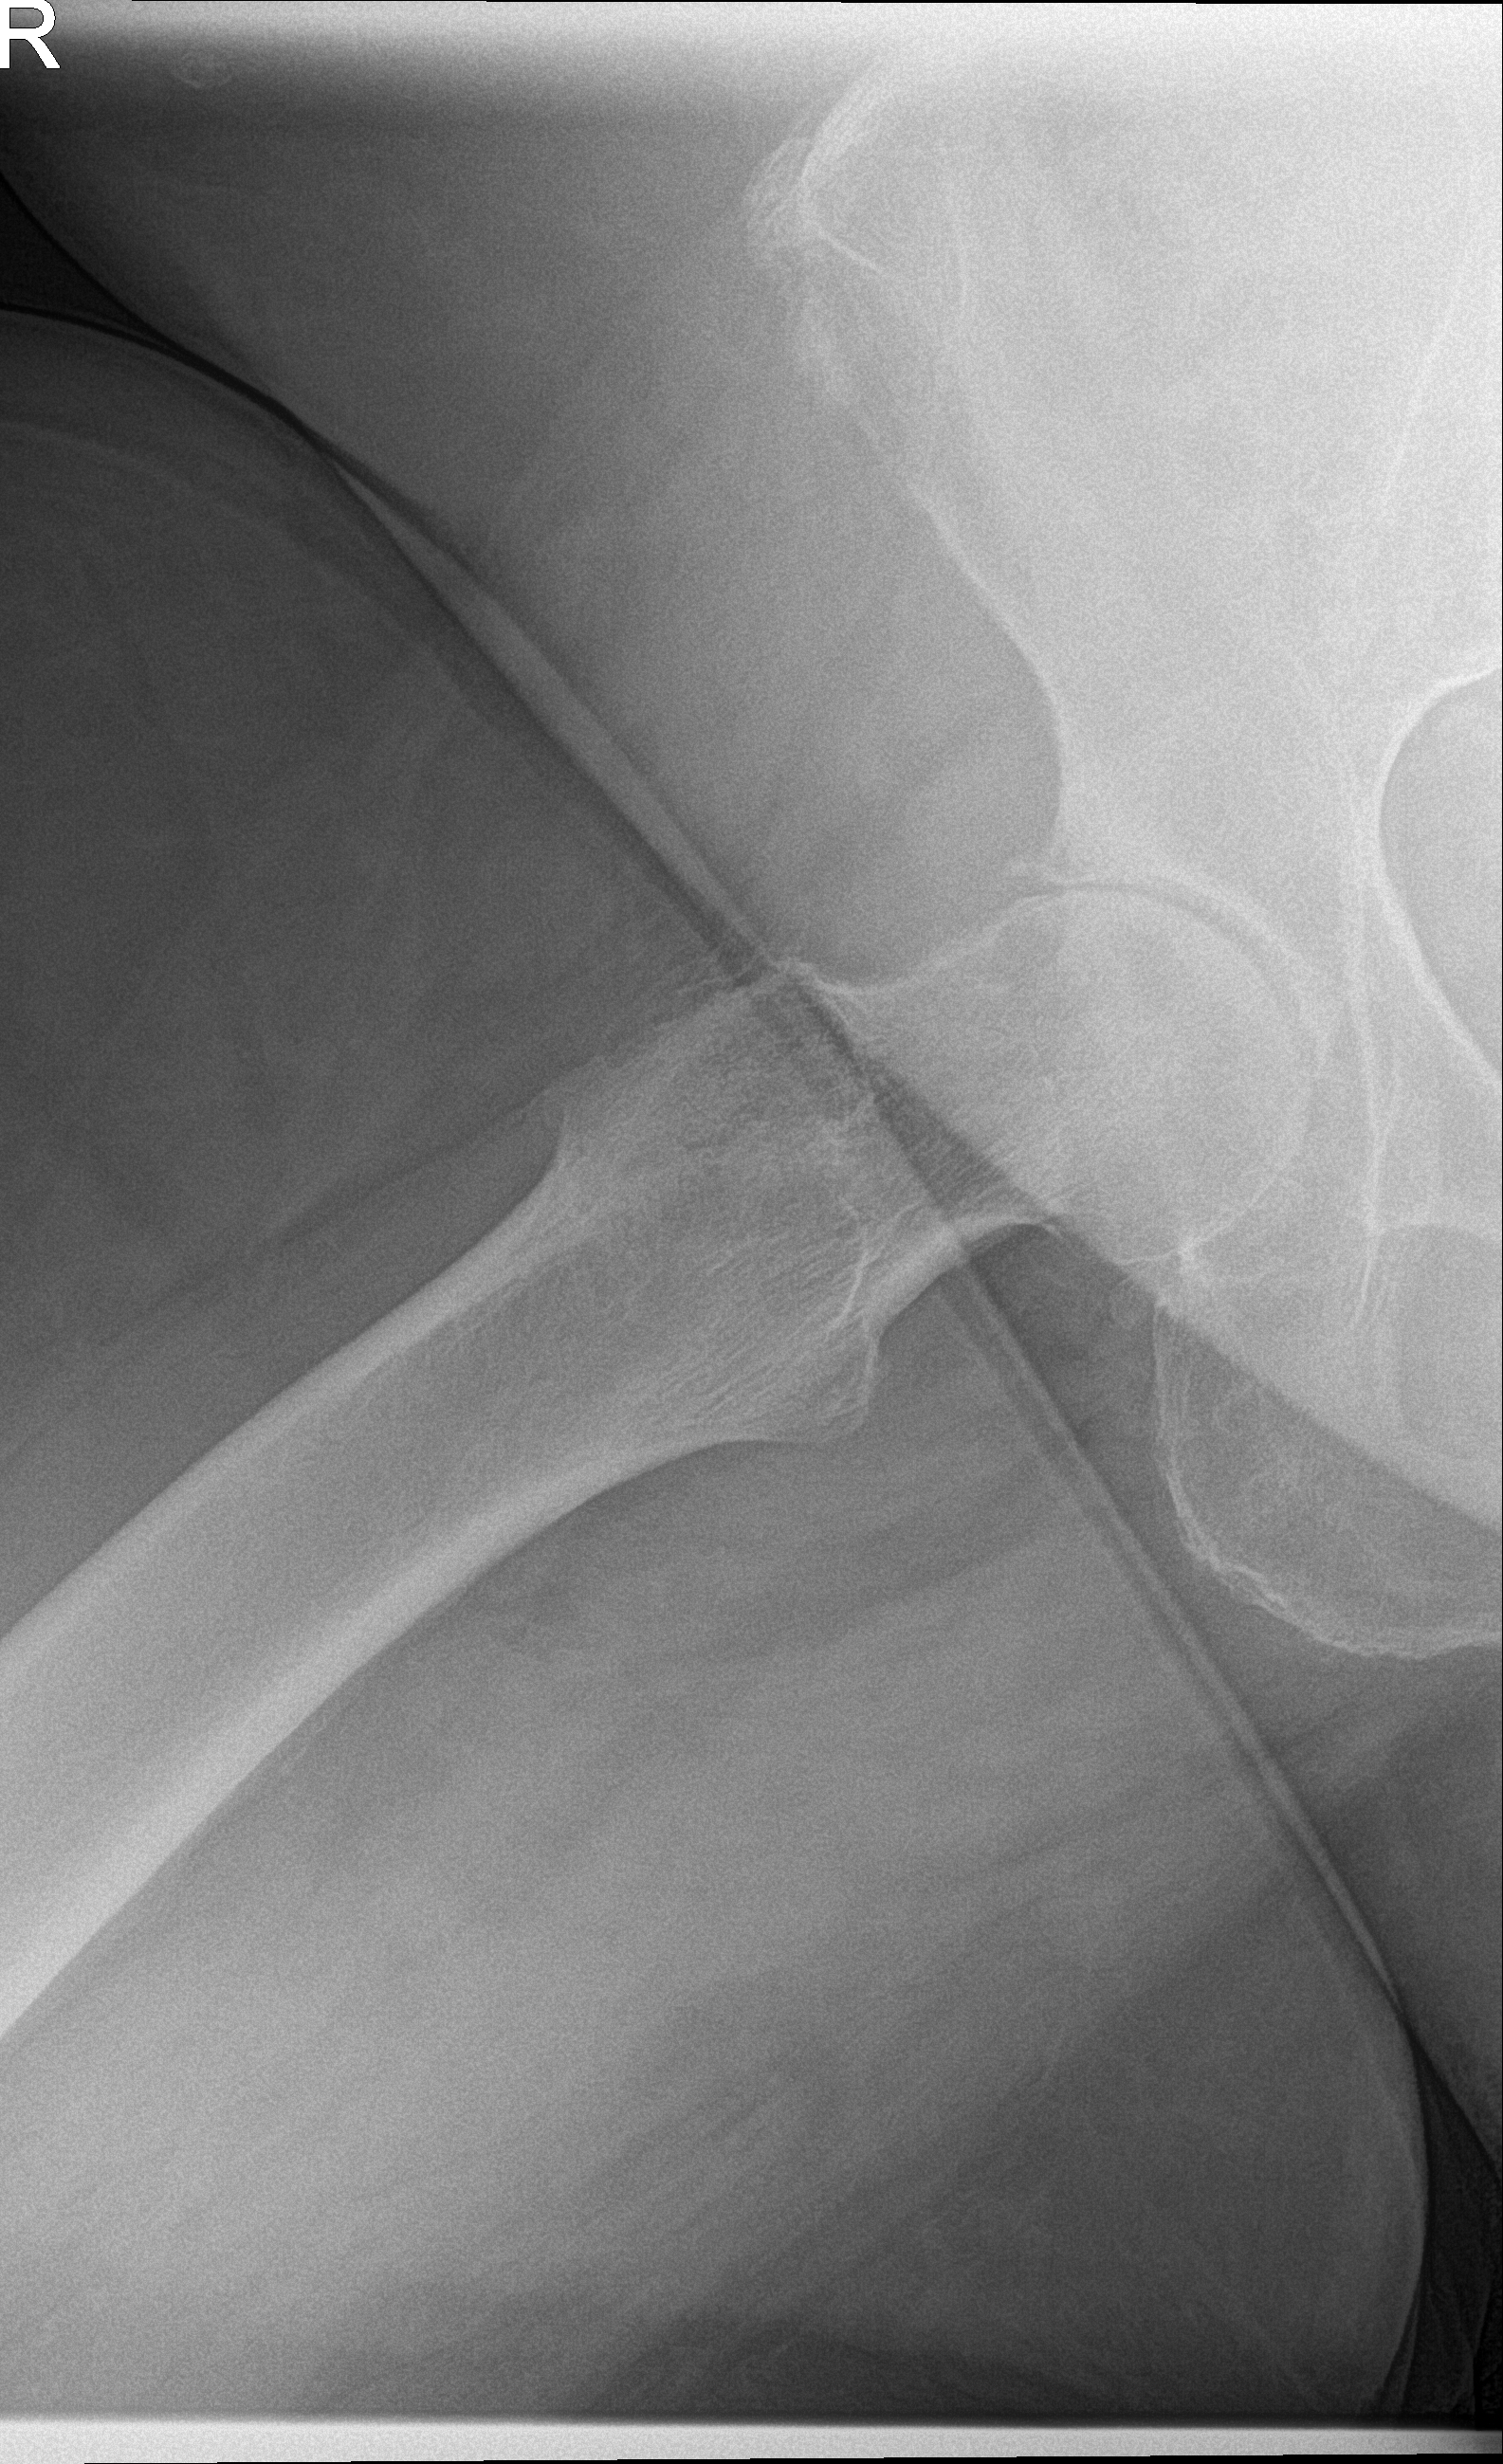

21.11.2025 - Luxiert

Röntgen November 2025

Prothesenkopf aus Pfanne luxiert

21.11.2025 - Luxation!

Becken 2025

Prothesenkopf luxiert nach medial/kaudal

Röntgen Hüfte rechts (aktuell)

DICOM JPEG HQ

Aktuelle Röntgenaufnahme der rechten Hüfte (2836x2336 px).

Röntgen Hüfte rechts

Aktuelle Aufnahme

21.11.2025

DICOM

Luxation der Hüft-TEP